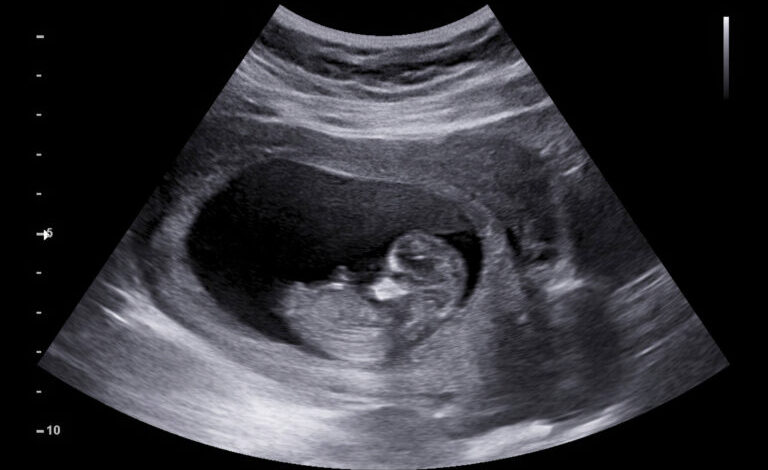

But that excitement soon turned into fear. During one of my routine prenatal checkups, the doctor scheduled an ultrasound to check on the baby’s development. At first, everything seemed normal, but as the doctor studied the screen, his expression changed. He became quiet, then serious. My heart started racing.

After the scan, the doctor told us something that shattered our hopes. According to the ultrasound, our baby was not developing properly. Some parts appeared incomplete, and the doctors were concerned about the child’s chances of survival after birth.